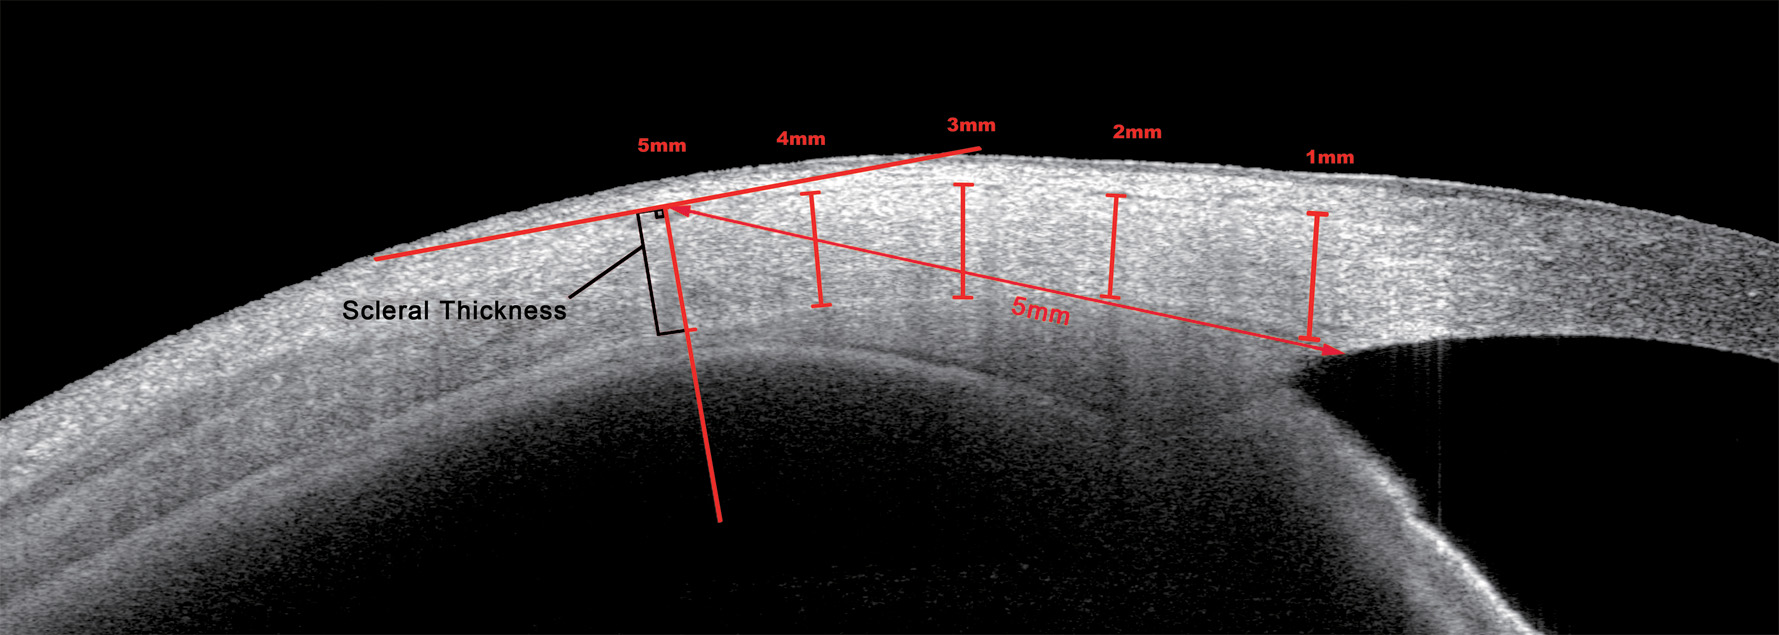

Figure 2 of Li, Mol Vis 2024; 30:229-238.

Figure 2. Measurement protocol of scleral thickness. The scleral thickness is measured vertically 1–5 mm posterior to the scleral spur.